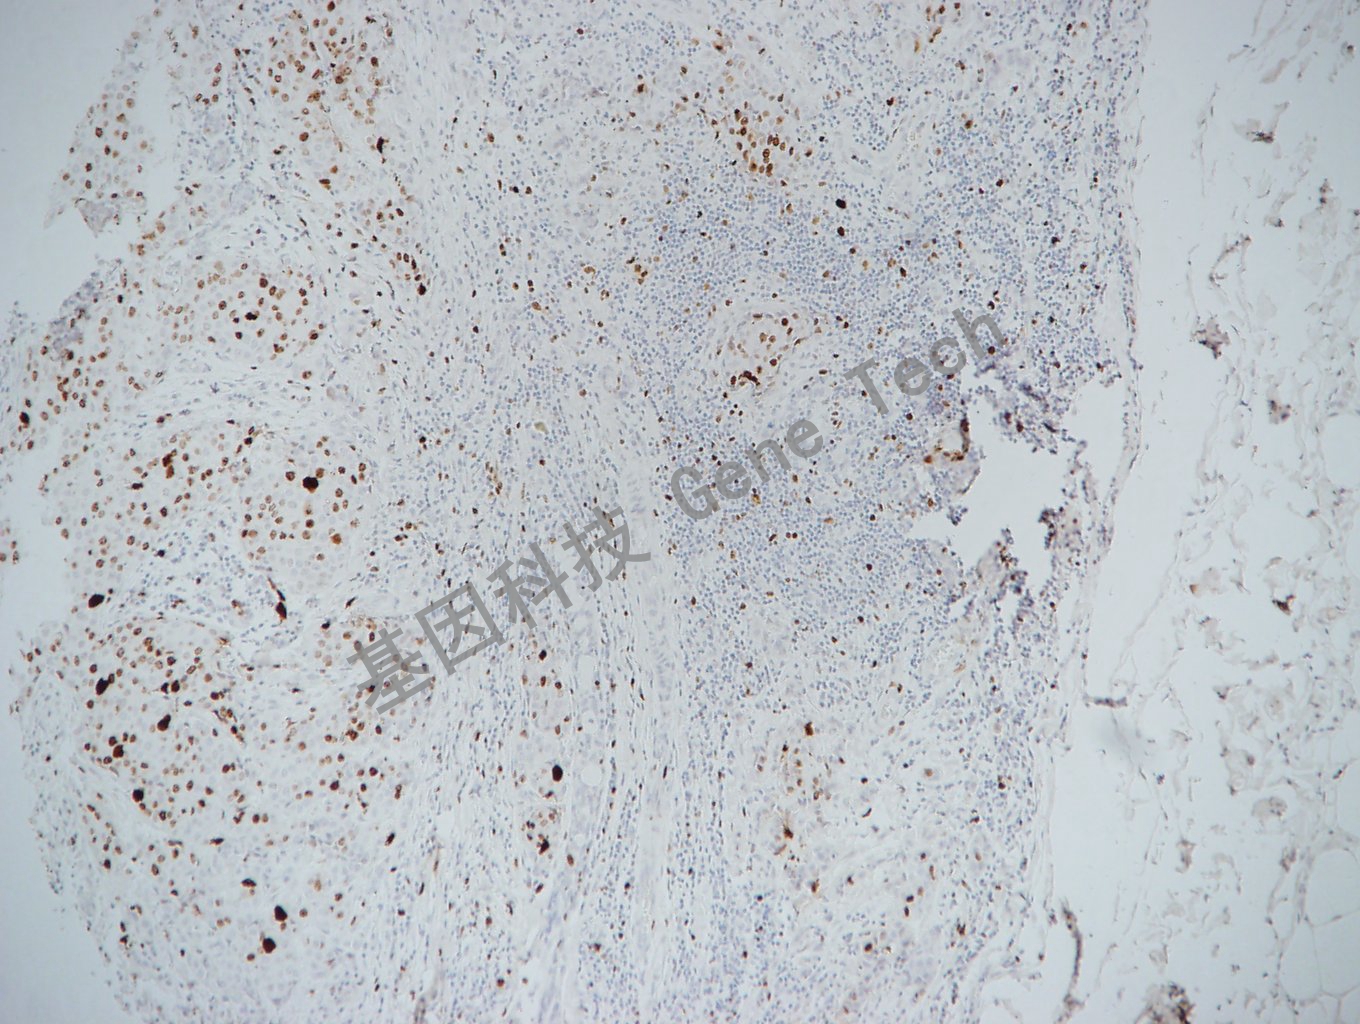

乳腺癌石蜡切片,用 Ki67(GT2101)染色,细胞核阳性,DAB 显色。

Ki-67可以识别出在细胞增殖周期G1、S、G2和M期的细胞,而处在G0期的细胞不着色。可判断细胞的增殖活性,是确定良恶性组织生长状态的标记。研究表明,它与乳腺癌的组织学分型、核分裂指数和淋巴结转移情况密切相关,由于Ki-67比PCNA更为直接反应细胞的增殖情况,因此常用于某些恶性肿瘤预后的一个重要参考指标。有助于判断淋巴瘤的恶性程度,高级别淋巴瘤Ki-67一般大于40%或50%。